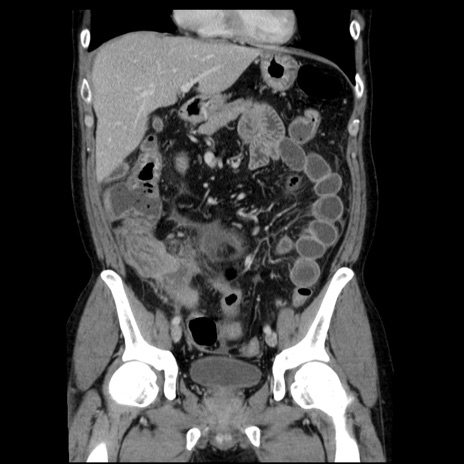

症例29(冠状断像)

【症例】40歳代男性

【現病歴】2日前から胃痛あり。徐々に周期的な激痛に変化した。本日になっても激痛があるため受診。

【身体所見】意識清明、BT 38-39℃台あり、腹部:膨満、やや硬、右下腹部に圧痛あり。

【データ】WBC 8500、CRP 23.26